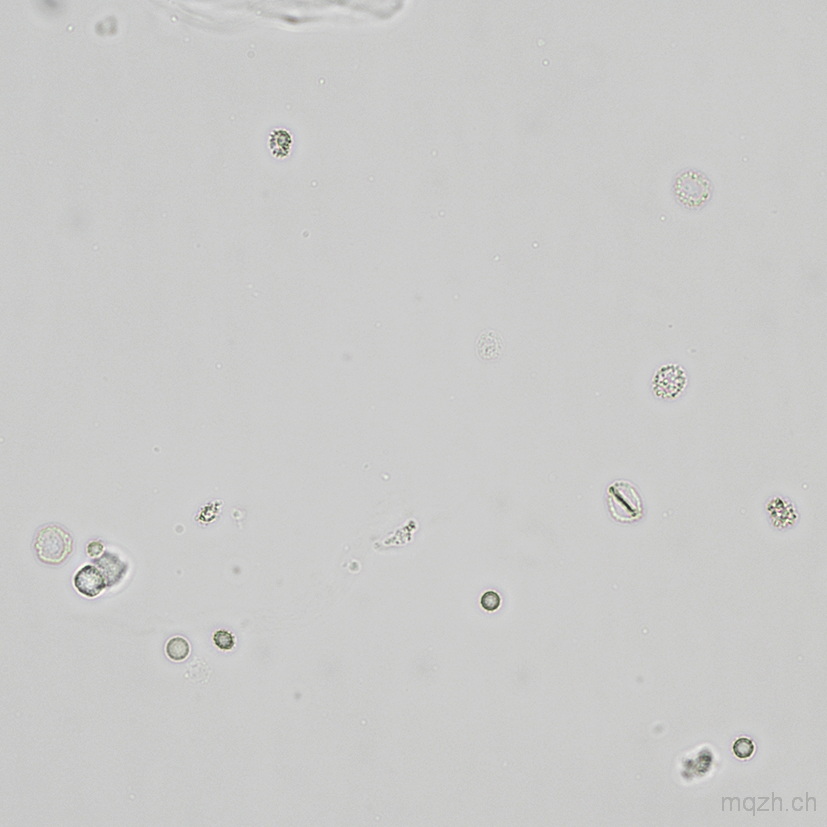

MQ 2025-4 Urinary Sediment U4